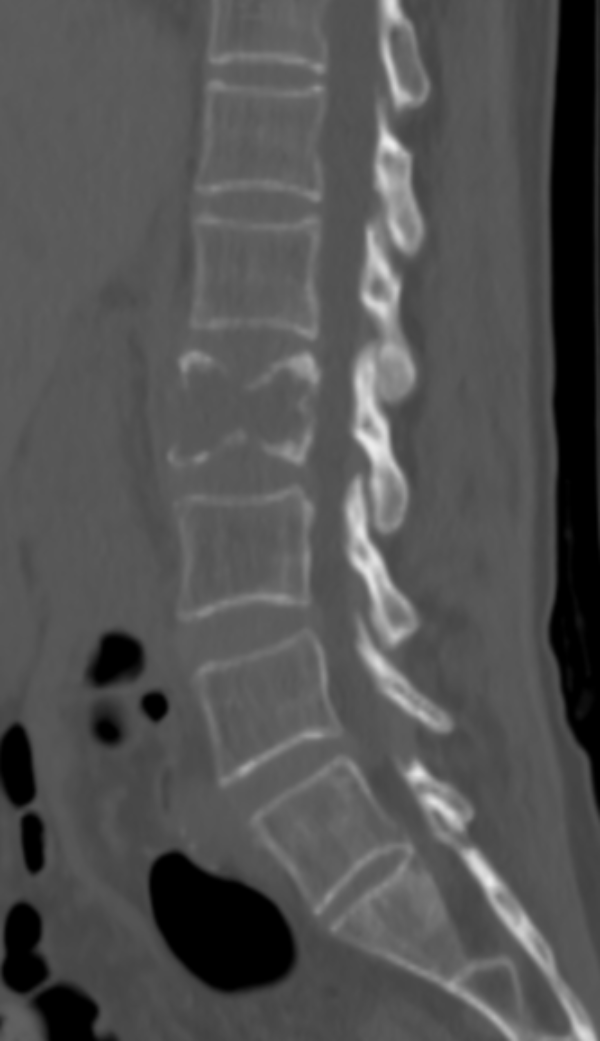

△ 術(shù)前CT:腰2椎體骨質(zhì)破壞,伴周圍軟組織腫脹,考慮骨轉(zhuǎn)移瘤。